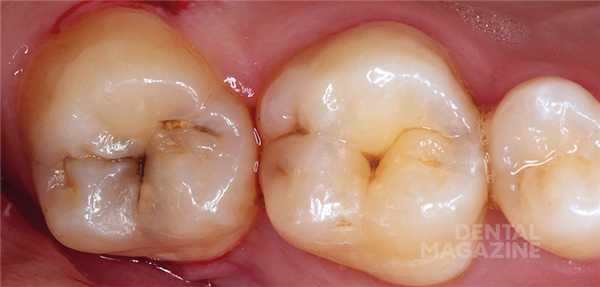

На рисунке 1 показана исходная ситуация.Классический фиссурный кариес зубов 16 и 17. Как и в большинстве подобных случаев, кариозный процесс протекает абсолютно бессимптомно.